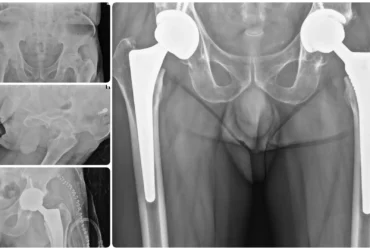

Bilateral AVN Hip Treated with Total Hip Replacement | Balanku Hospital

Sheikh Sameer with bilateral avascular necrosis of the hip underwent successful bilateral total hip replacement at Balanku Hospital...